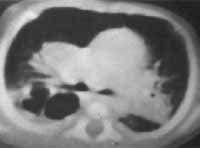

La RX de Tórax al ingreso mostró imágenes hiperlúcidas bilaterales de predominio derecho con opacidad basal derecha con componente atelectásico (Figura 1). Se considera neumonía necrotizante, y se realiza estudio de VIH siendo negativo, citomegalovirus, toxoplasma, sífilis negativo. Tres hemocultivos negativos, urocultivo negativo, LCR citoquímico normal con cultivo negativo.

La radiografía de tórax puede mostrar diferentes patrones, adenomegalias, atelectasias, infiltrados parenquimatosos persistentes y muy rara vez pueden cavitar como fue en el caso de este paciente (7,8).

Las lesiones persistentes en la radiografía de tórax deben hacer sospecha de la enfermedad, particularmente en el caso de las atelectasias.